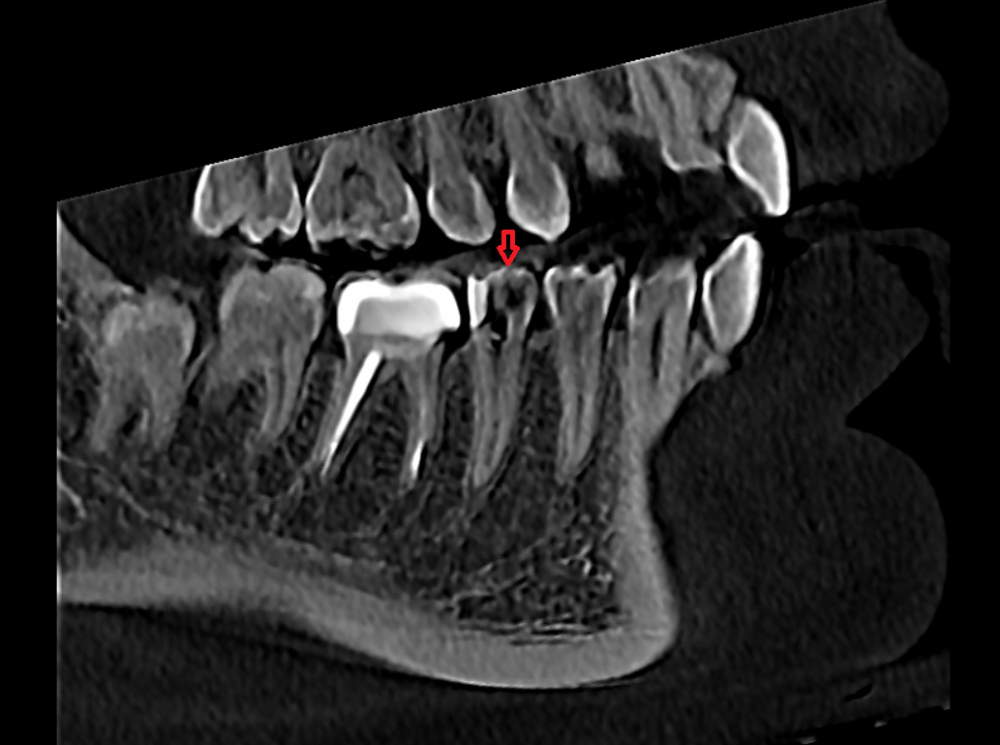

Доброго времени суток, уважаемые форумчане и врачи! Хочу попросить вашего участия в теме, тк ситуация выглядит нестандартной. Дано: 5ый нижний зуб слева, рядом коронка на 6ом.

6. Сделала КТ, врач говорит, что с зубом все ок, нижнечелюстной канал задет быть не может. Сегодня запломбировали постоянным материалом, но симптоматика по жжению, пульсации(при надкусывании) и лёгкому онемению осталась.

На фото - 5ый нижний зуб рядом с жевательной коронкой. Подскажите, пожалуйста, в чём может быть проблема.

Добрый день. До магистрального нерва по кт далеко, его задеть точно не могли. Насколько хорошо запломбировали канал оценить невозможно, т.к.  не приложили снимок после лечения.